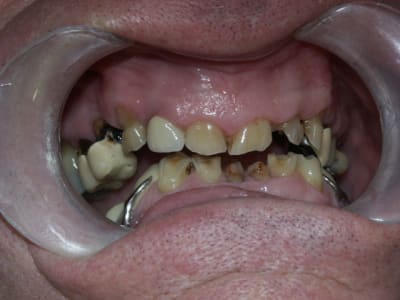

un cas très galère pour la rentrée... nouvelles photos et radios!!

Qu'est ce que je peux proposer comme plan de traitement?

j'avoue que je suis un peu paumé...

Le constat est le suivant, corrigez-moi si je me trompe:

on a eu des extractions non compensées à la mandibule qui ont provoquées des égressions des dents maxillaires postérieures.

une abrasion +++ du bloc antérieure avec égression "physiologique" au fur et à mesure de l'usure.

On a ainsi un décalage important (comme une marche d'escalier) de la courbe d'occlusion (Spee) entre le secteur antérieur et postérieur.

La difficulté de la thérapeutique consistera à rattraper le mieux possible ce décalage pour avoir une courbe d'occlusion "harmonieuse".